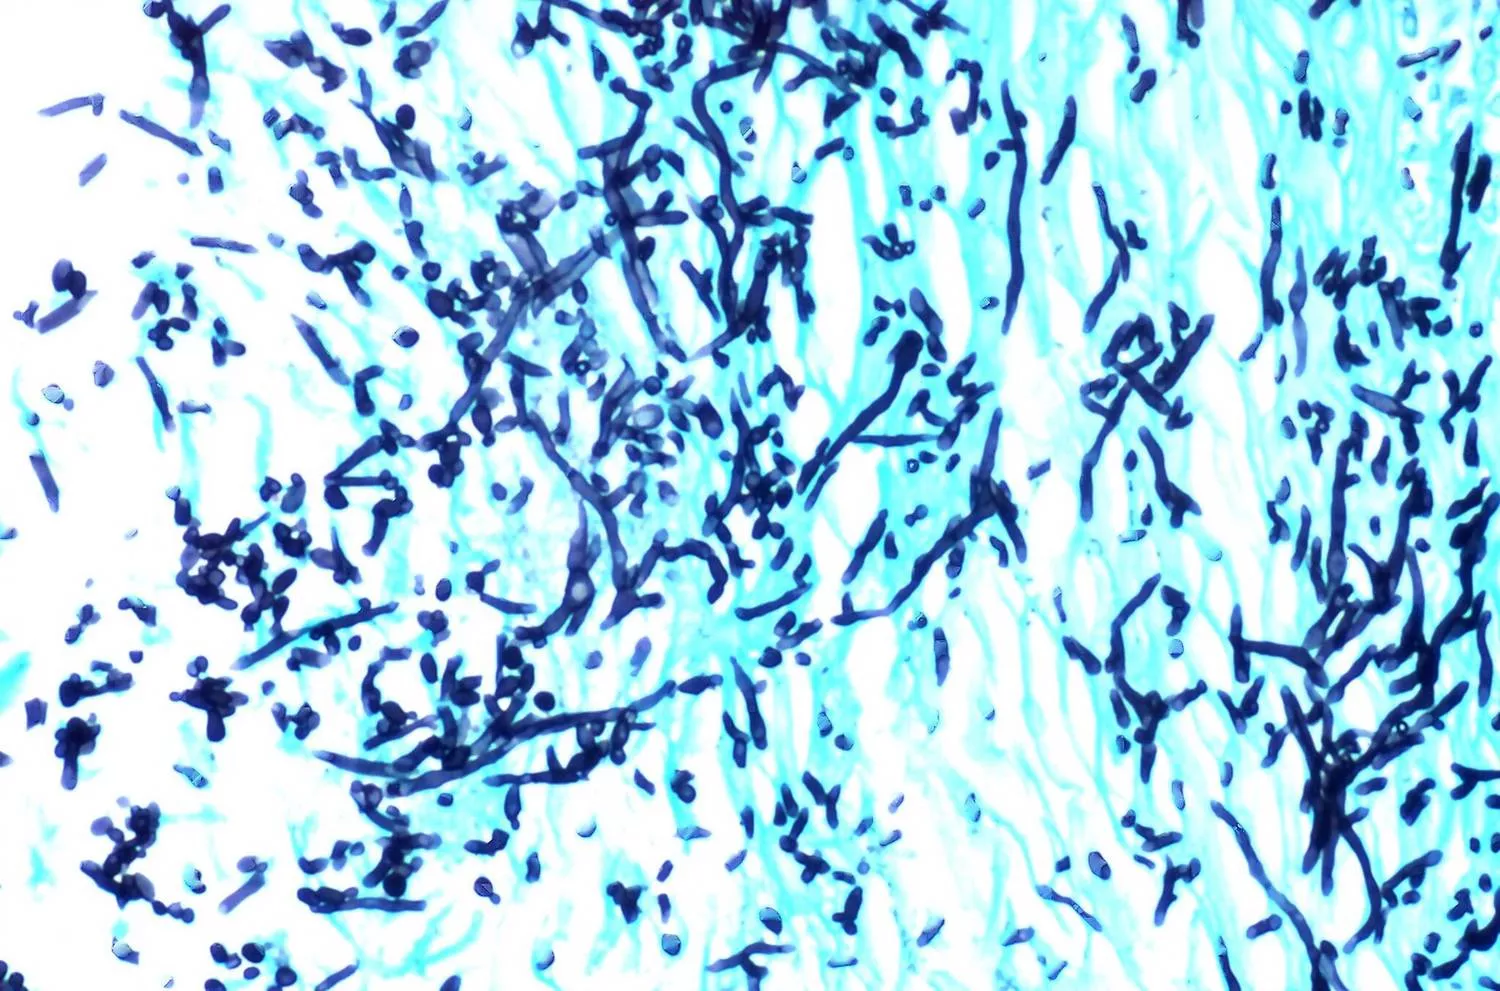

Megfestett candida mikroszkóp alatt

Megfestett candida gomba mikroszkóp alatt (szerző: Yale Rosen, USA; liszensz: CC BY-SA 2.0, Wikimedia Commons)